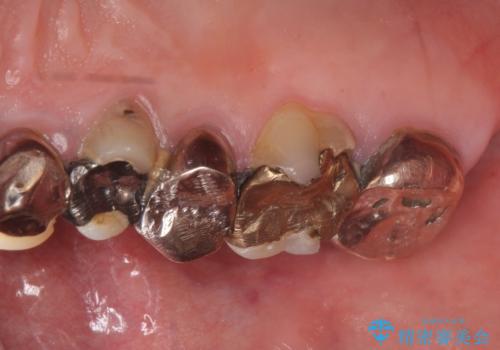

- 歯がない左側でものが咬めず、右側で咬むと歯が痛むので診て欲しいといらっしゃった方の症例です。

根尖病変が認められる歯は再根管治療を行い、歯根が破折していた左上4は抜歯しました。

インプラントは希望されなかったため、左側は1番から7番のロングスパンブリッジによる補綴を行いました。